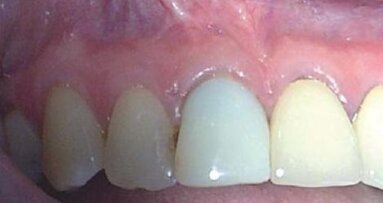

Jednym z czynników, który zmniejsza szanse powodzenia jest występowanie zapalenia przyzębia wierzchołkowego przed leczeniem. W przypadku braku zapalenia przyzębia wierzchołkowego wskaźnik powodzenia po 10 latach dla pierwotnego leczenia endodontycznego oraz leczenia rewizyjnego wynosił 92-98%. Jeśli przed leczeniem występowało zapalenie tkanek okołowierzchołkowych, wskaźnik powodzenia zmniejszał się, osiągając po 10 latach wartość 74-86%. Na tej podstawie jednoznacznie widać, że możliwe jest uzyskanie wygojenia dzięki rewizji leczenia endodontycznego, co pozwala na zachowanie naturalnych zębów pacjenta (Ryc. 1a-c). Wprawdzie alternatywna metoda leczenia, jaką jest wszczepienie implantu może być skutecznym sposobem zastąpienia brakującego zęba, jednak nadrzędny cel powinno stanowić zachowanie w zdrowiu naturalnych zębów.

Podchloryn sodu w stężeniu 6% ma skuteczne działanie przeciwbakteryjne, rozpuszcza tkanki i niszczy biofilm bakteryjny. Te cechy płynu sprawiają, że doskonale nadaje się do usuwania przetrwałych bakterii i pozostałości tkanek. Użycie koferdamu w celu odizolowania pola zabiegowego stanowi standardowe postępowanie podczas leczenia endodontycznego. Brak użycia koferdamu może być głównym czynnikiem przyczyniającym się do powikłań po leczeniu. W dalszej części artykułu opisano przypadek ilustrujący możliwość skutecznej rewizji i wygojenia zęba, który był pierwotnie poddany niepełnej preparacji (Ryc. 3a-c).